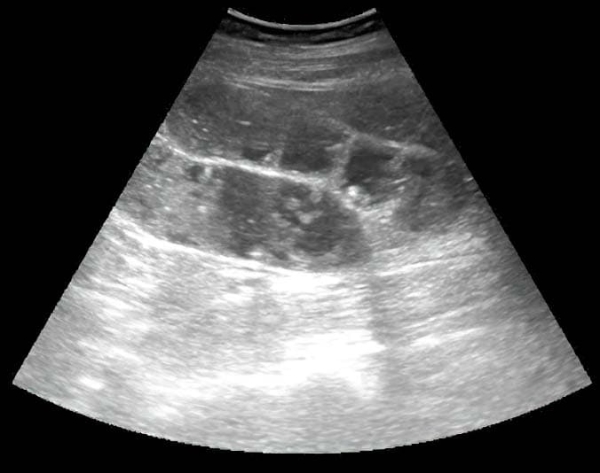

Характерные признаки острой кишечной непроходимости при ультразвуковом исследовании: петли тонкой кишки заполнены жидкостью, расширены до 25–30 мм и более; перистальтика маятникообразная или отсутствует; визуализируются циркулярные складки (в этом отличие тонкой кишки от толстой); может определяться свободная жидкость межпетельно (не всегда) (см. рис. 19).

Рисунок 19. Острая кишечная непроходимость.

Пример описания: «В гипогастрии визуализируются расширенные до 30–40 мм петли тонкого кишечника, наполненные жидкостью, с вялой маятникообразной перистальтикой; определяется свободная жидкость межпетельно» (см. рис. 20).

Рисунок 20. Острая кишечная непроходимость.